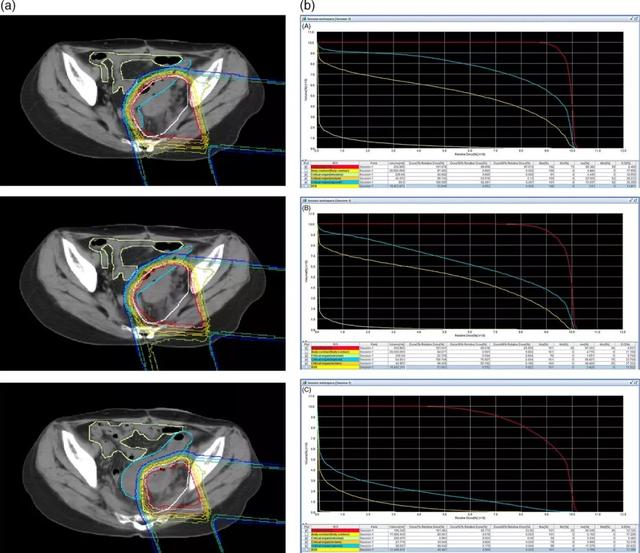

卵巢癌质子治疗,卵巢癌质子治疗优势,卵巢癌质子治疗价格费用多少钱 卵巢癌

卵巢癌卵巢癌质子治疗,卵巢癌质子治疗优势,卵巢癌质子治疗价格费用多少钱

卵巢癌质子治疗,卵巢癌质子治疗优势,卵巢癌质子治疗价格费用多少钱腹胀,竟是卵巢癌的征兆Ashley Sutton一直对自己的生活非常满意,2010年夏天,她和丈夫结婚20周年,同时,她的工作也出现了很大的转机,一切都向着好的方向发展。最开始,Sutton感觉有时会胃胀气并且腹部变得越来越大,好像怀孕了一样,Sutton以为是自己近期吃了太多的垃圾食品导致体重